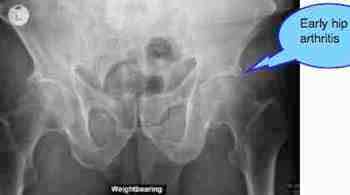

What muddies the water is the degenerative changes in both hips, worse left. Could that be the cause of the groin pain? An emphatic NO. The range of motion of the hips is full and virtually painfree.

The short left leg is readily visible.